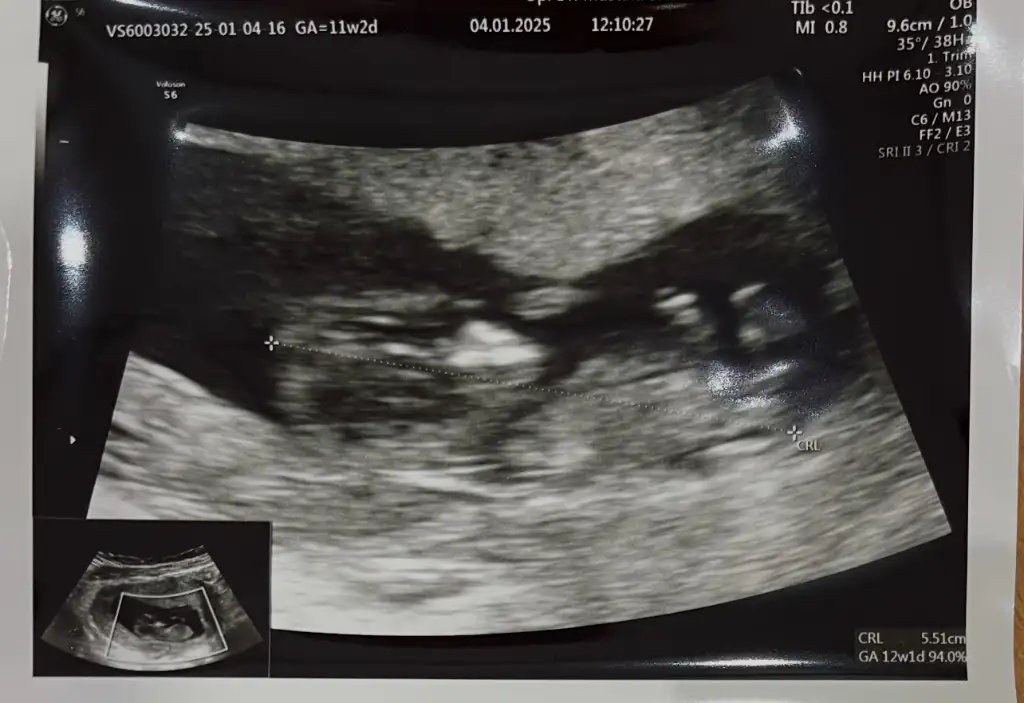

Merhaba kızlar, 11+1 ultrasonuma göre cinsiyet tahmininiz olur mu acaba 🥰